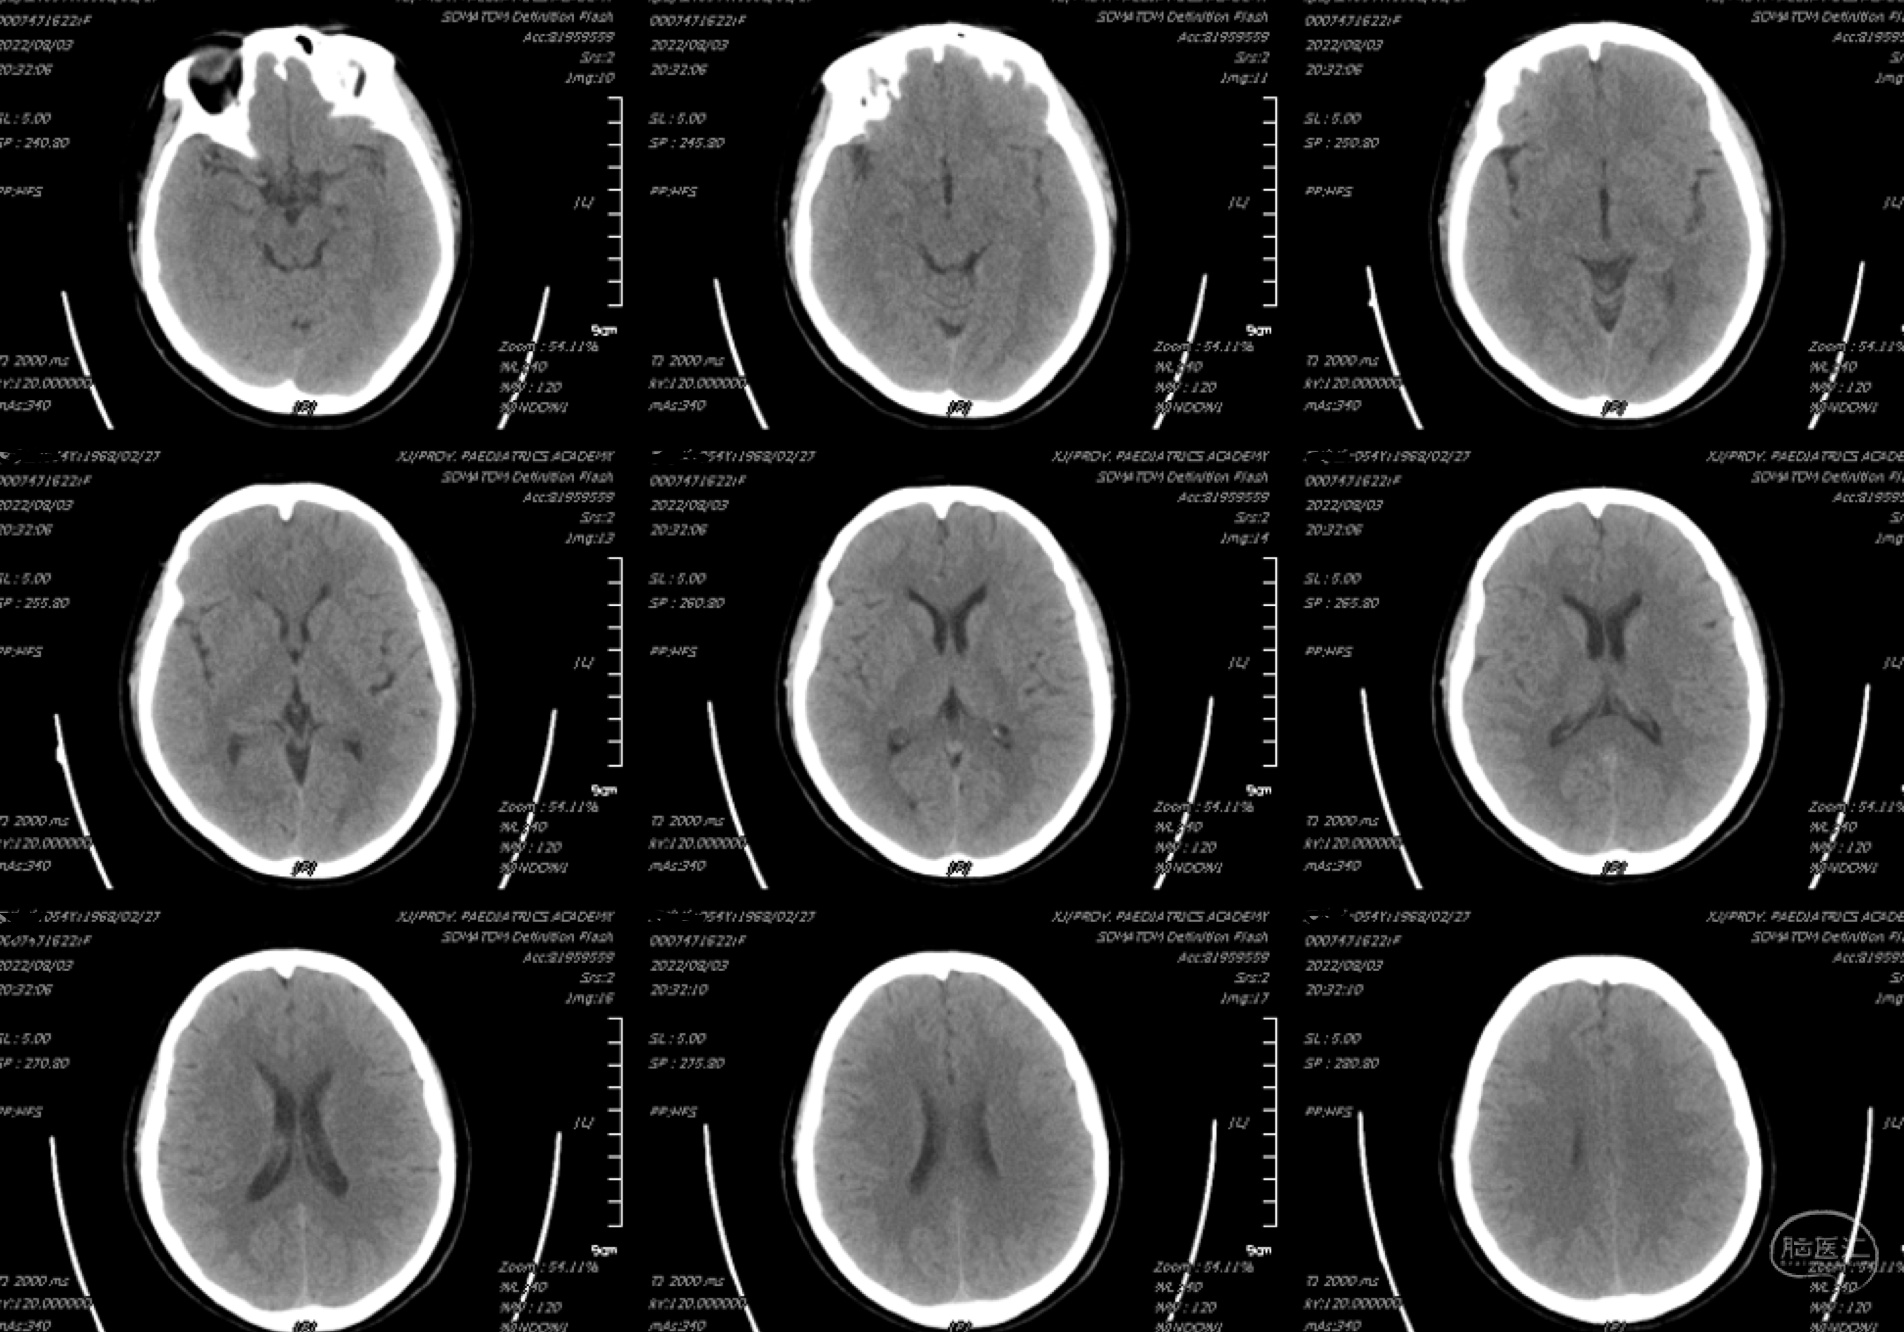

术后患者麻醉复苏,神志清楚,言语流利,视力正常,双瞳等大等圆,左右3.0mm,对光反射灵敏,四肢活动自如,肌力肌张力正常,病理征阴性。给予补液、对症治疗,术后当日头颅CT(8月1日 22时05分):颅内情况稳定。

术后患者恢复良好,复查头颅CT(8月3日):颅内情况稳定。术后5天康复出院。期待6月复查结果!